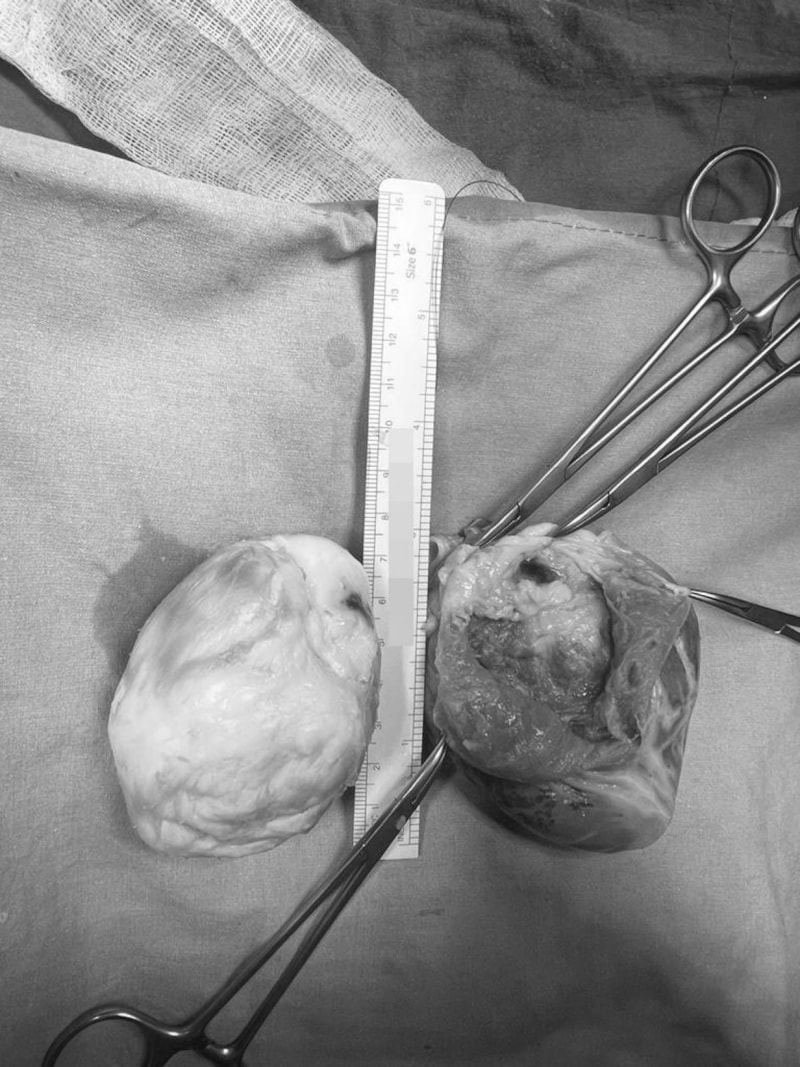

Ekin Ada kızımızla 32 haftada anne karnındayken ilk olarak tanıştım. Fetal EKO'sunda bir kalp tümörü tespit edilmişti. Kızımız doğdu, ondan sonra 3 ila 6 aylık aralarla izlemeye başladık. Kalp içindeki tümör yaşı büyüdükçe, kalple beraber büyüyordu. Bu tümörlerin bir kötü tarafı da ritim düzensizlikleri yaratmaları. Ani ölüm riskinin çok yüksek olduğu vakalar bunlar. Tümörün büyüklüğü neredeyse kalp kadar olmuştu. 7 santimlik bir tümör, Ekin Ada'nın kalbi 8 santim uzunluğundaydı zaten. Sol karıncıktaki tümörün bir büyük tehlikesi daha vardı. Önemli bir koroner arter damar, tümörün içinden geçiyordu.

Çok dikkatli çalışmamız gerekiyordu o nedenle kalbi yerinden söktük, damarlarından ayırdık ve masanın üzerine yatırarak (kalp vücuttan ayrıyken) ameliyata devam ettik. Göğüs boşluğu tamamıyla boş kaldı, 'kalpsiz' bir durumda makineye bağlı takip edildi. Kalbi masanın üzerinde sol karıncığa hasar vermeden, hem kasları hem arterleri koruyarak açtık. Dr. Yılmaz Zorman ile beraber nefesimizi tuttuk, ince ince, soğan kabuğu soyar gibi kalp kasından tümörü ayırdık. Tümörün içinden geçen o ince, bir milimetrelik koroner damarı bulduk ve onu da titiz bir şekilde tümörden ayırarak kalbi tamamen temizledik. Onarılmış kalbi tekrar yerine taktık.